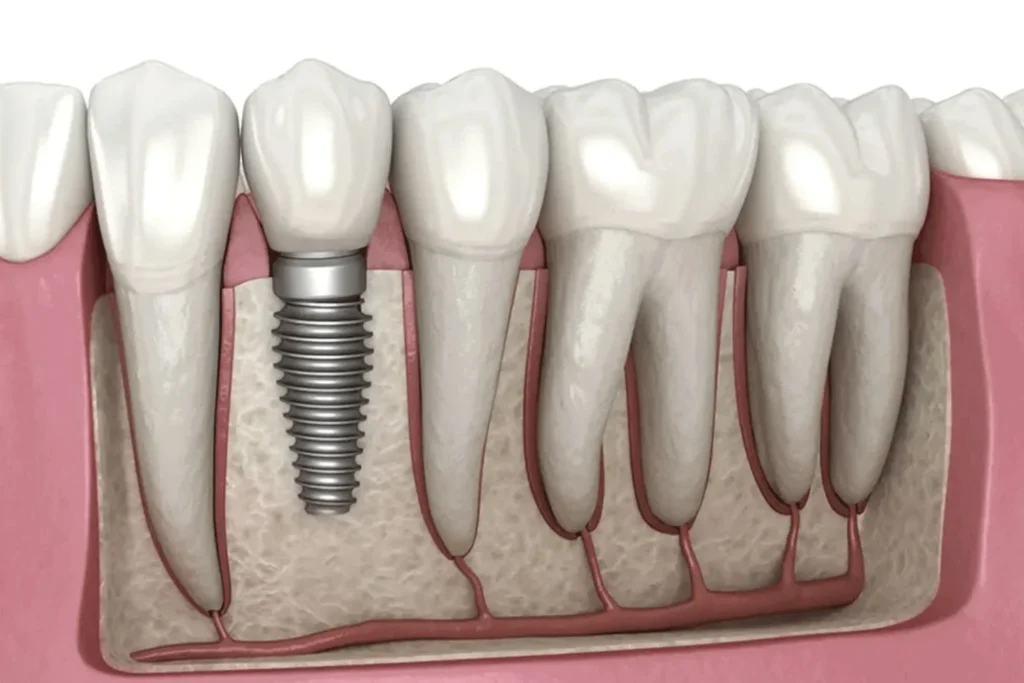

ایمپلنت دندان به عنوان مطمئنترین و محبوبترین روش برای جایگزینی دندانهای از دست رفته شناخته میشود. این روش شامل قرار دادن یک پایه از جنس تیتانیوم (فیکسچر) به عنوان ریشه مصنوعی درون استخوان فک است و روکش ایمپلنت دندان بر روی آن قرار میگیرد.

ایمپلنت دندان یک درمان دائمی و بسیار مطمئن برای کاشت دندان است و مزایایی چون جلوگیری از تحلیل استخوان فک، برگرداندن عملکرد (فانکشن) و زیبایی، و عدم آسیب به دندانهای مجاور را به همراه دارد.